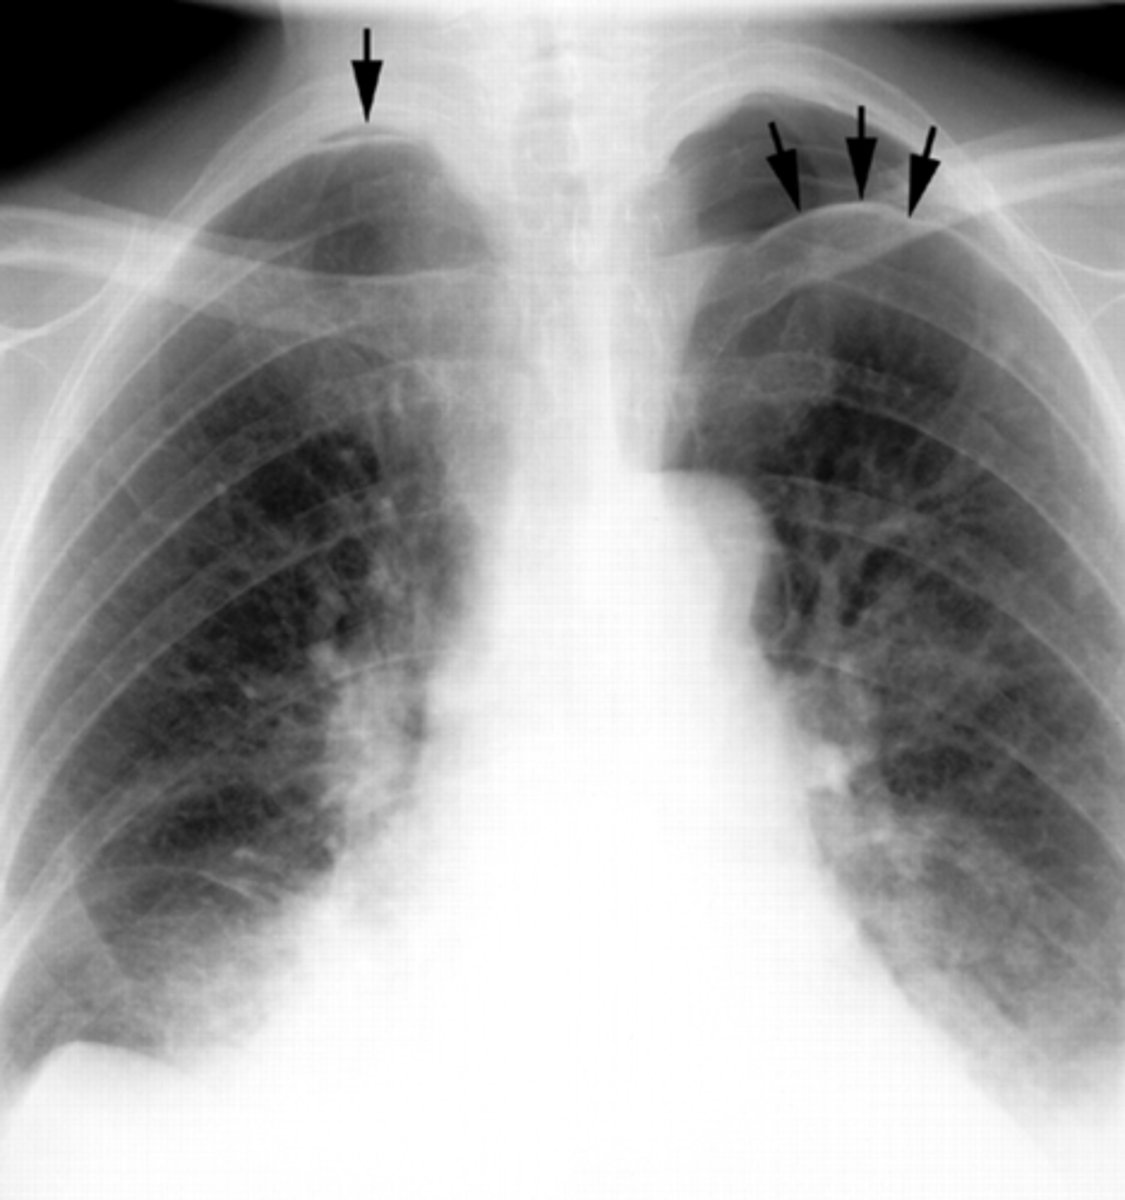

RUL bullae

Bullae RUL